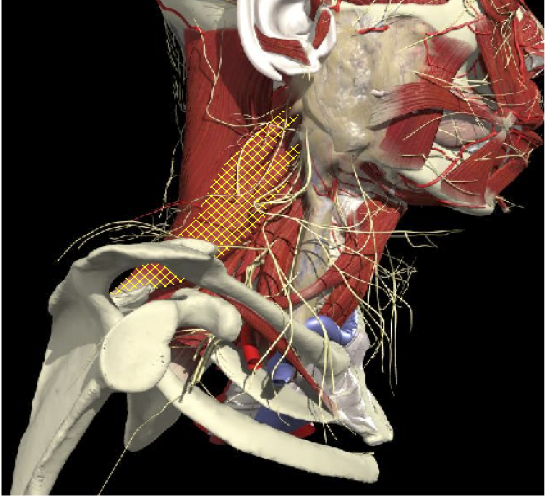

ACCURACY OF MUSCLE LOCALIZATION

- Muscles deep

- Not easily identified by surface landmarks

- Not palpable on examination

ACCURACY OF LOCALIZATION LEVATOR SCAPULAE

LOCALIZATION OF MUSCLES IN DEEPER LAYERS

Layer 1

Layer 2

Layer 3

Splenius Capitis

Semispinalis Capitis

Longissimus Capitus

Semispinalis Cervicis

ACCURACY OF LOCALIZATION – DEEPER LAYERS

INJECTION SITES